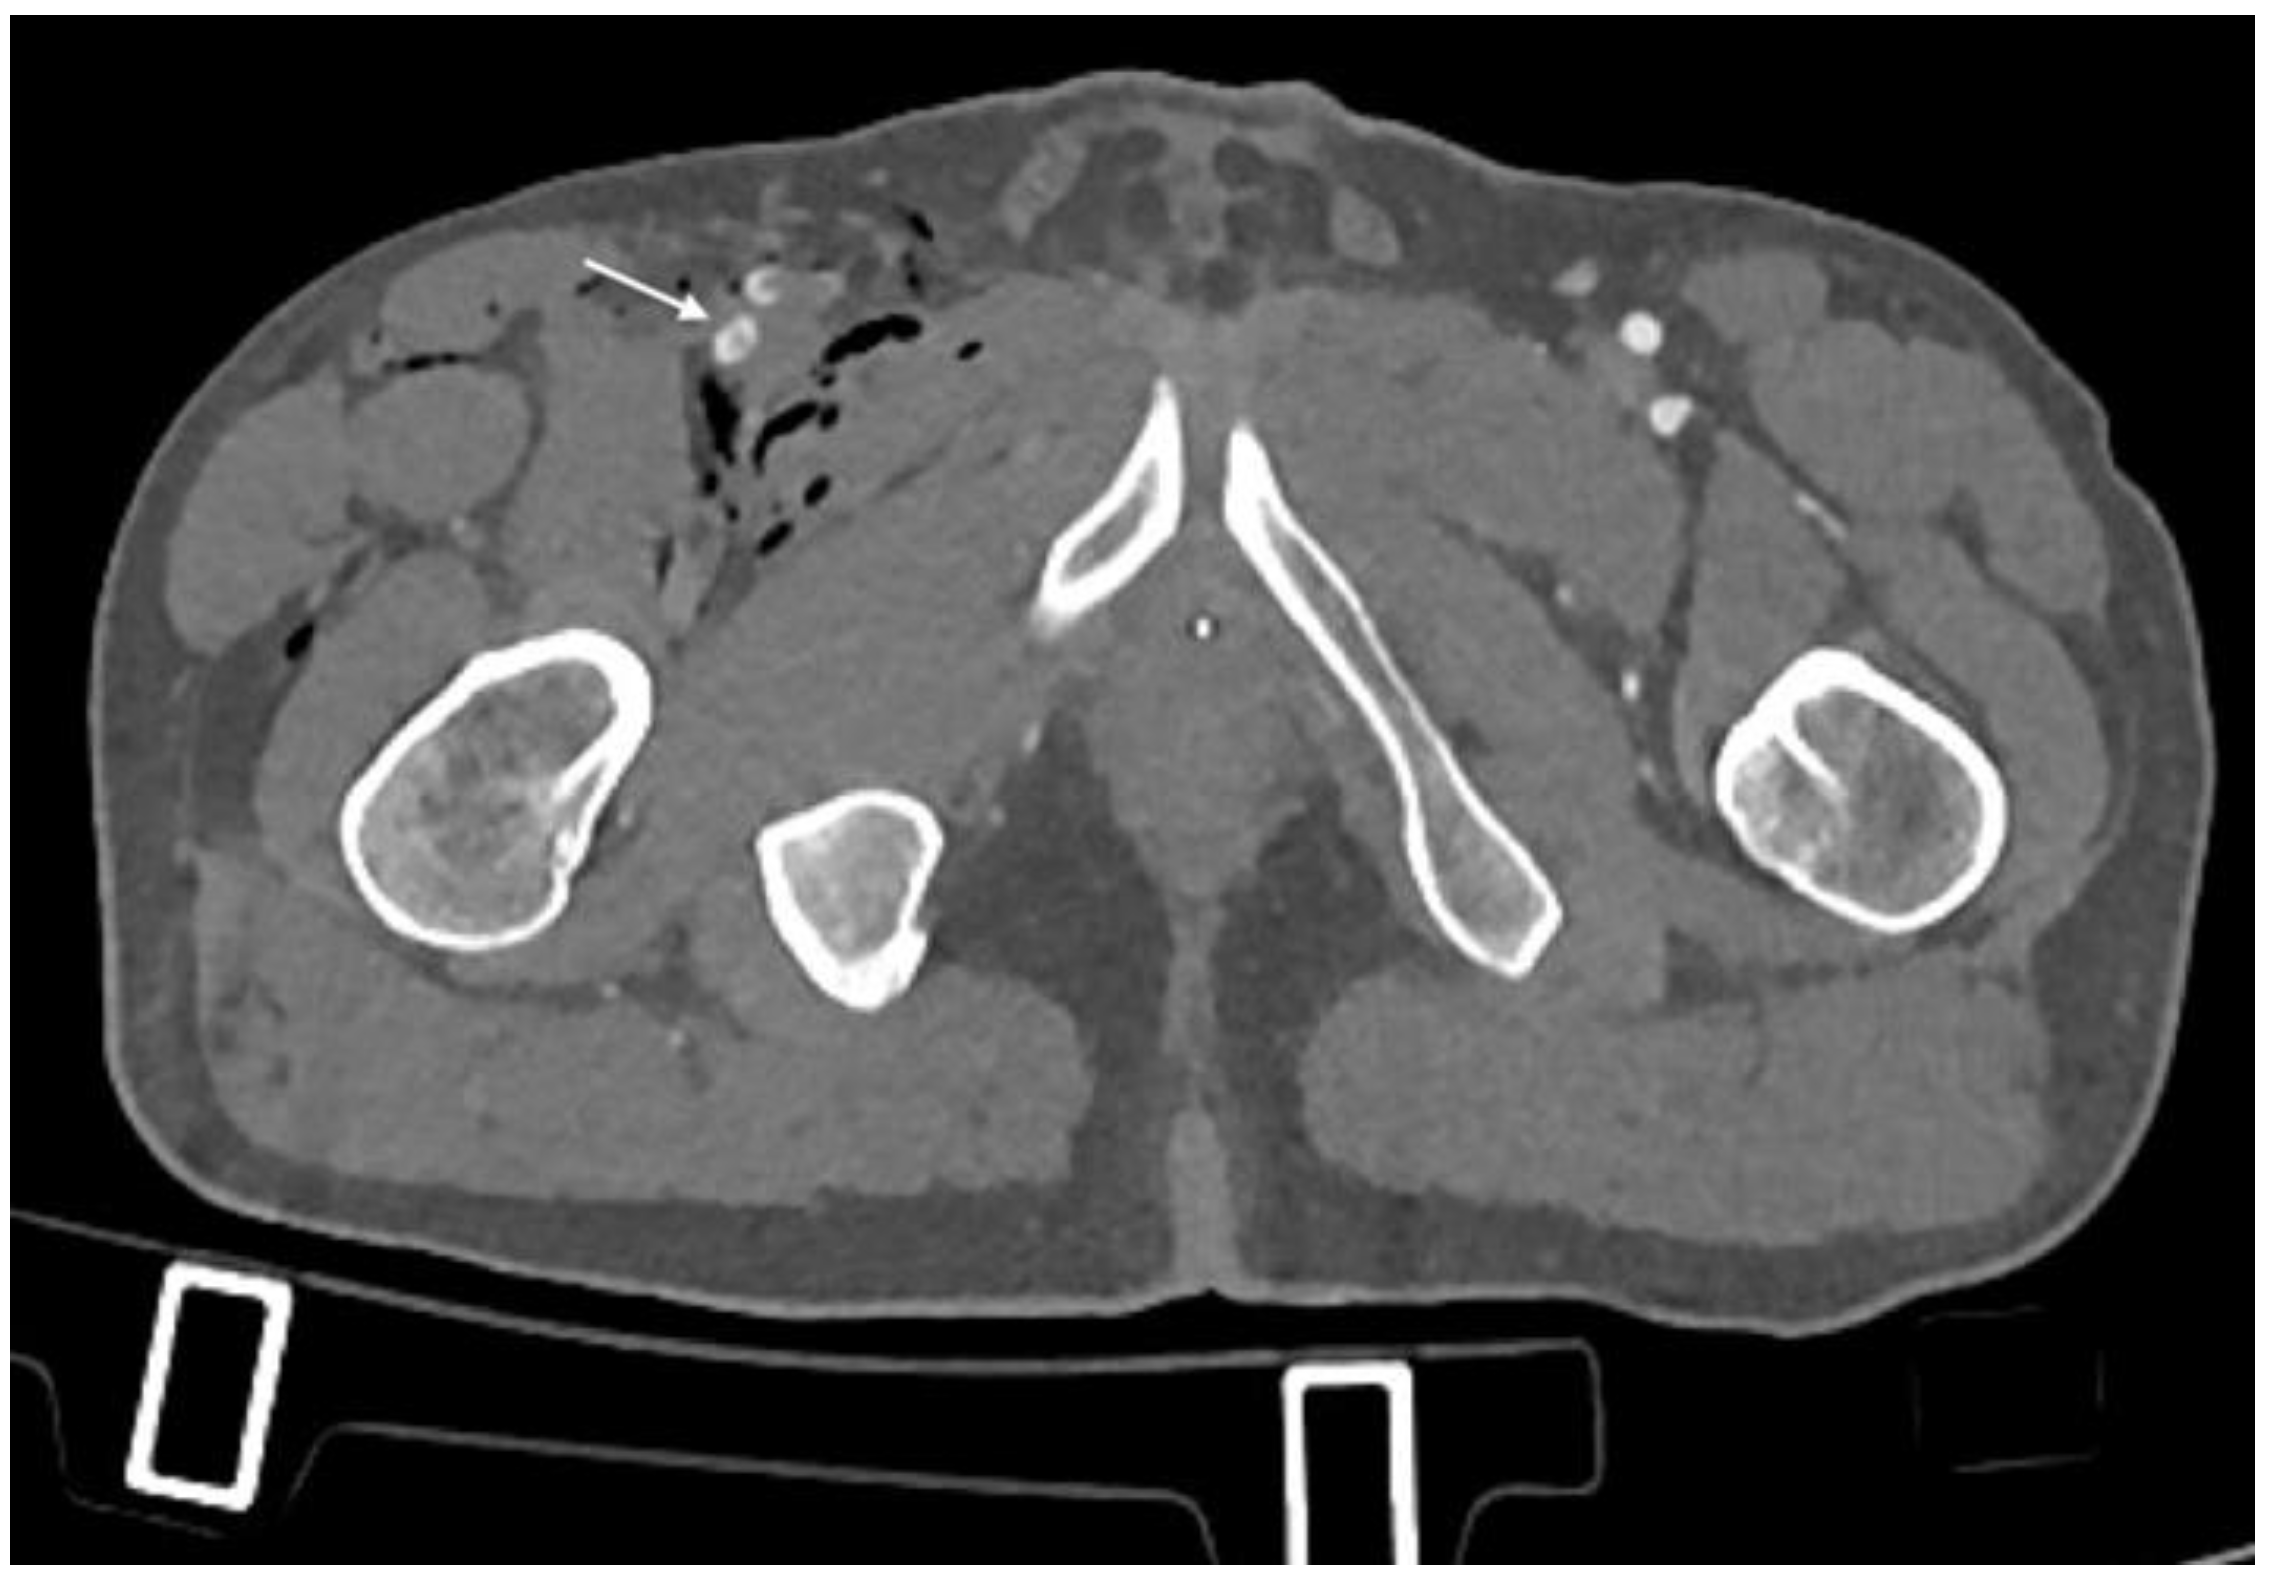

3.2. CTA Imaging Findings